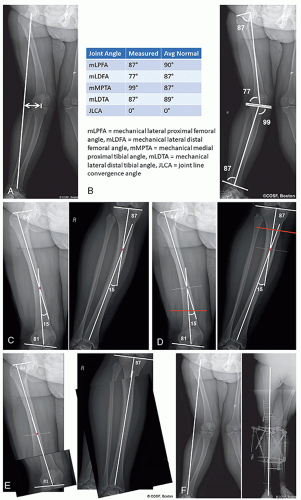

A standing hips-to-ankles radiograph with patellas forward is the workhorse image for assessing coronal plane deformity and limb-length. Full-length lateral images of the limbs with the knee in maximal extension is helpful for assessment of sagittal plane deformity if present

Radiographs are assessed for mechanical axis, joint angles (mechanical or anatomic), magnitude of deformity or length difference, localization of the apex of the deformity, and visualization of any planned correction (Figure 25.1)